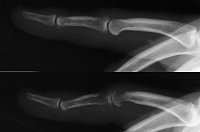

Radiographs taken shortly after the initial injury (top) compared to those shortly before surgery (bottom) show osteolysis consistent with osteomyelitis: